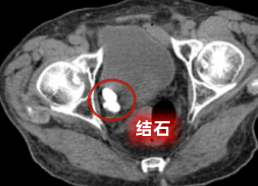

在多学科紧密配合下,手术团队精准定位膀胱内多发结石,利用钬激光将结石逐一击碎并顺利取出,同时精准处理前列腺增生问题,全程操作平稳顺利。术后,在医护团队精心护理与个体化康复指导下,张爷爷尿频、血尿、夜尿频繁等困扰已久的症状得到明显改善,饮食、睡眠及排尿情况逐步恢复正常,对治疗效果十分满意。